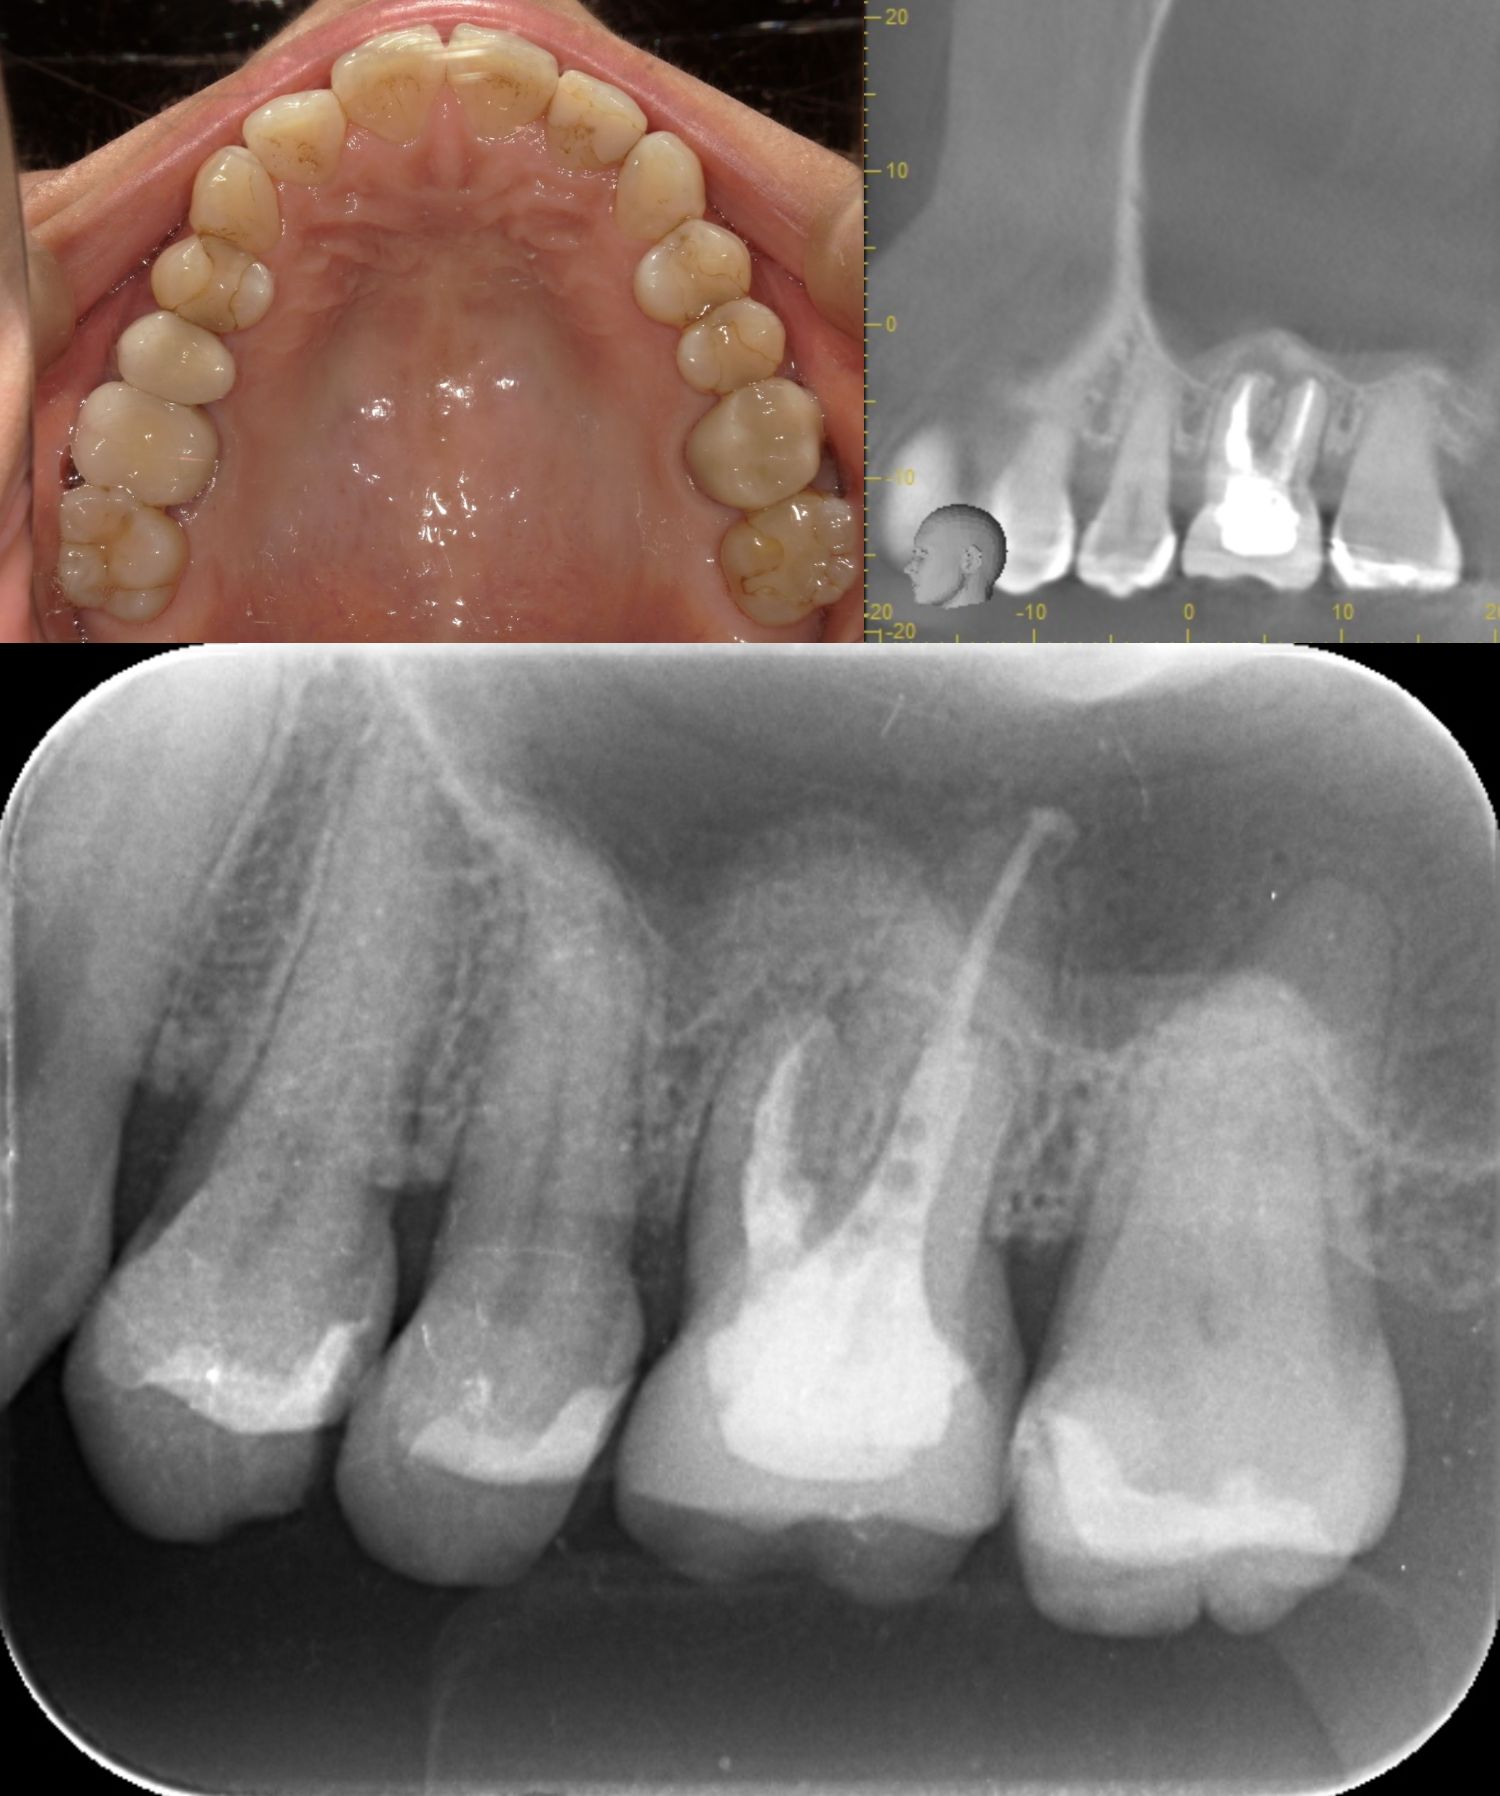

KE2205様

| 通院時年齢 | 46歳 | ||||||

|---|---|---|---|---|---|---|---|

| 性別 | 女性 | ||||||

| 通院目的 | 咬んだ時の歯の根の違和感 | ||||||

| 診断 | 左上6根尖性歯周炎 | ||||||

| 処置内容 (または主訴) | 感染根管処置から被せ物装着 | ||||||

| 通院期間 | 7か月(3か月で終わるものが来院が遠方により長期になった) | ||||||